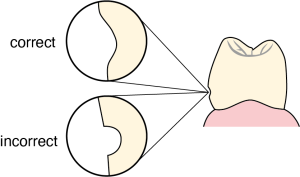

The angle between the base of the rest seat and the line drawn from the tooth’s proximal surface parallel to its long axis must be smaller than 90° in order for the forces acting on the prosthesis to be transmitted vertically (Figure 10-32).